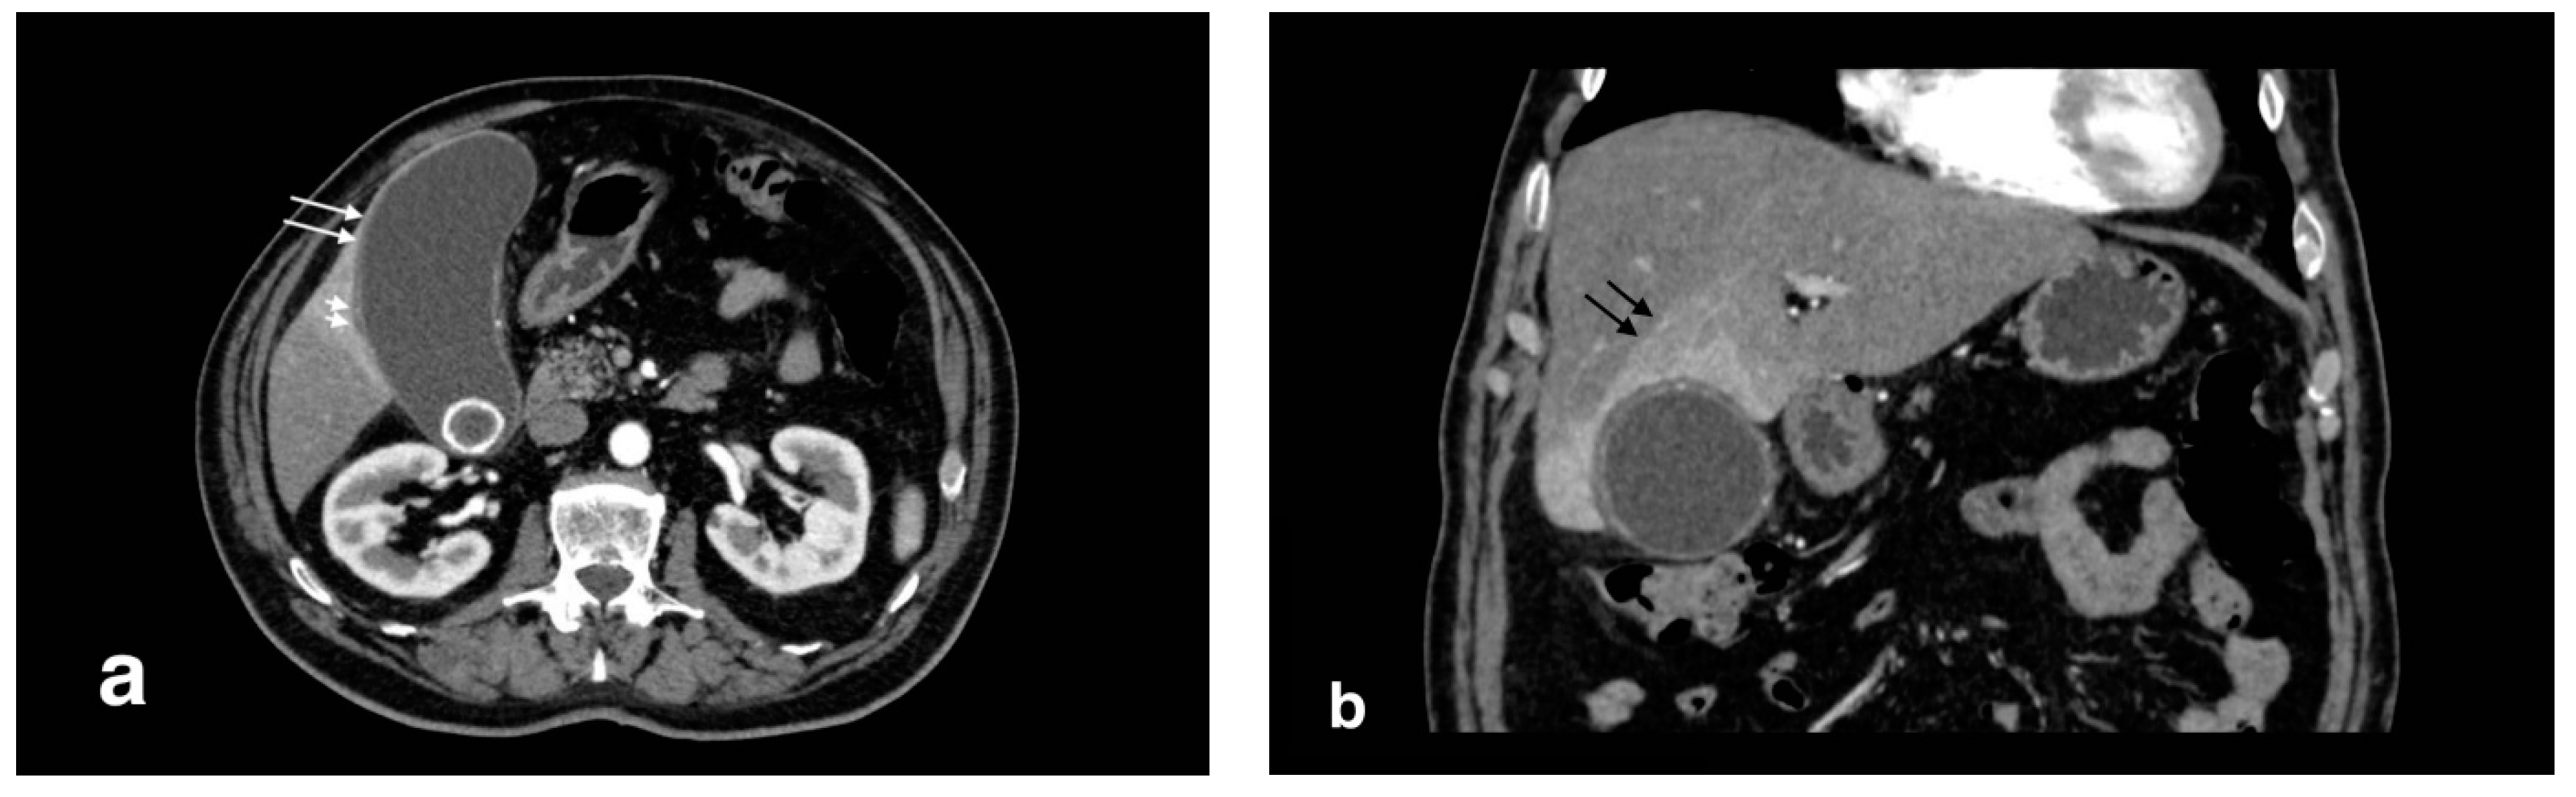

Figure 1.

Acute uncomplicated calculous cholecystitis: (a) overdistended gallbladder with diffuse wall thickening and hyperemia (white arrows) and pericholecystic fluid (arrowheads), (b) pericholecystic parenchymal enhancement (black arrows).